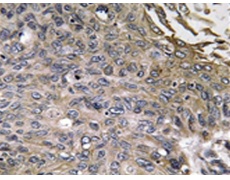

IHC |

IHC positive control: |

Human lung carcinoma tissue |

IHC Recommend dilution: |

50-100 |